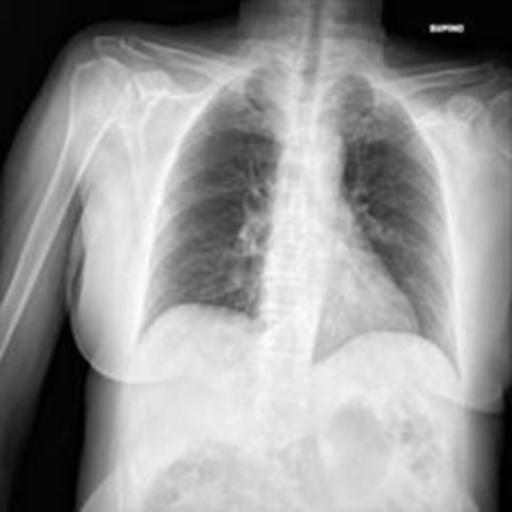

The dataset chosen in this paper is an open-source dataset, the dataset is selected from the open-source database, the database contains 150 lung X-ray images and their corresponding 150 masks, and we select four of them for presentation, the results are shown as follows, the four images in the first row are the original images of the lung X-ray, and the images in the second row in the corresponding position are their corresponding masks, as shown in Fig. 1.

Figure 1. Partial data.